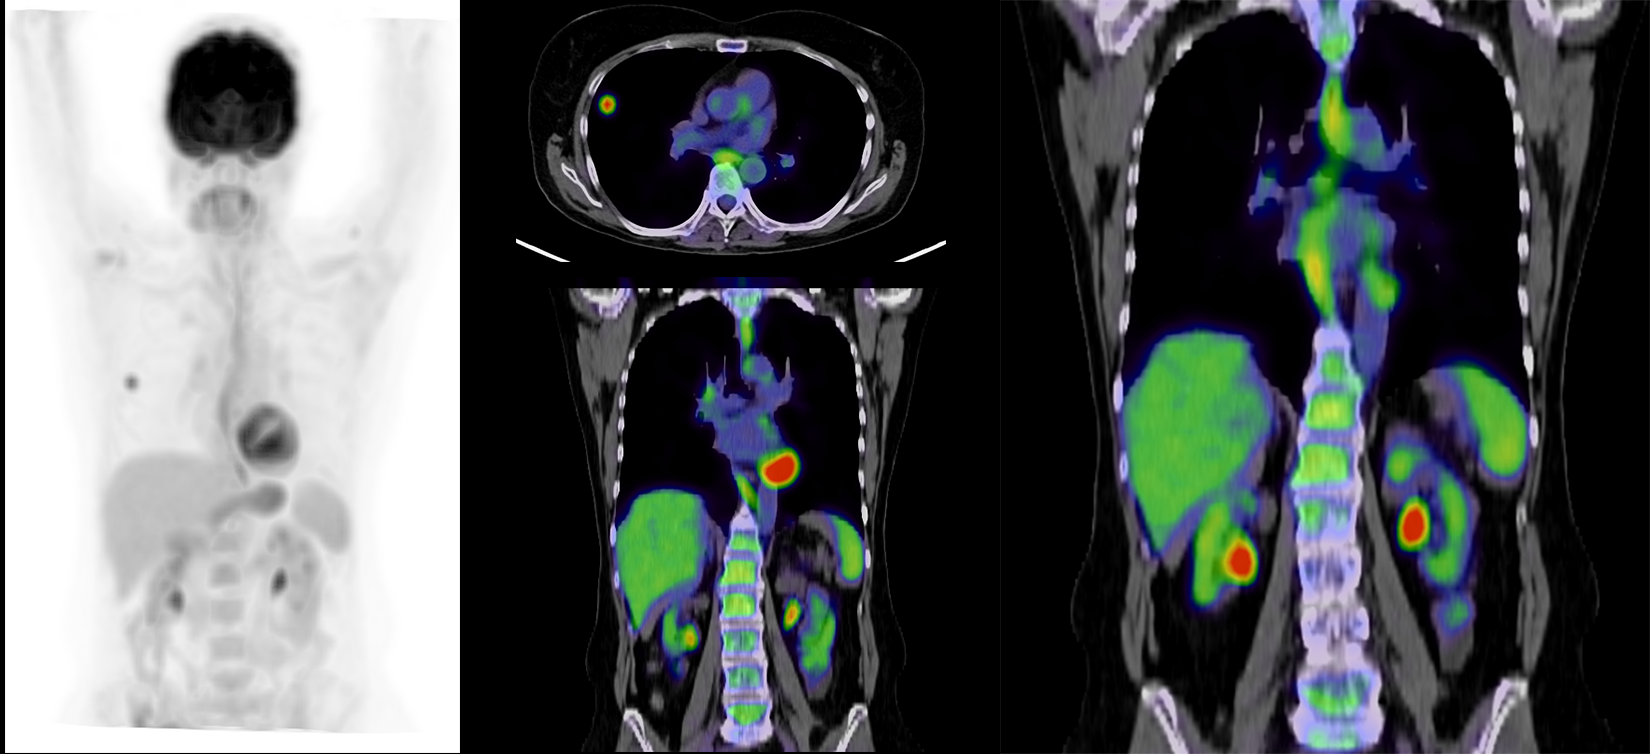

PET CT

What best describes the findings on the PET CT?

There is increased FDG uptake in the right hilum and right middle lobe lesion. The FDG in the bilateral renal hila represent physiologic excretion.

A PET CT can evaluate for tumor radiotracer uptake, nodal involvement, and metastases.

This lesion is unlikely a benign nodule like a hamartoma considering the spiculated margins. Squamous cell lung cancer is characteristically central. Small cell lung cancer is usually diffuse when diagnosed as it metastasizes early. This young patient without smoking history who is presenting with a peripheral lung nodule most likely has an adenocarcinoma.

This is a 39-year-old female without smoking history presenting with a peripheral lung nodule with spiculated borders. This is likely an adenocarcinoma. The patient should be referred to a pulmonologist. She may undergo PET CT and endobronchial ultrasound for further characterization. If the lesion is confirmed to be a T1N0M0 (no nodal involvement or metastases), this patient may require a lobectomy with radiological surveillance.